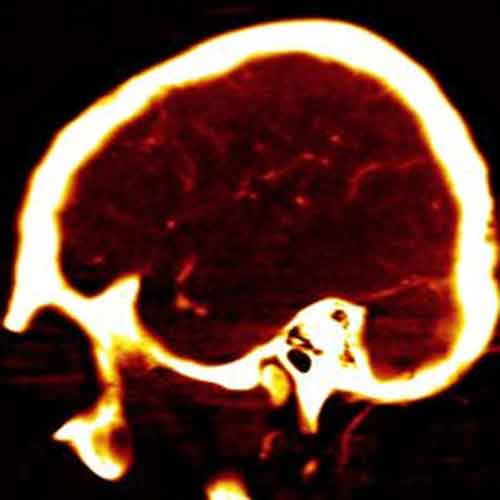

L’EMORRAGIA SUB-ARACNOIDEA – La patologia presa in esame dalla ricerca coreana è stata l’emorraggia sub-aracnoidea (ESA), sanguinamento che si verifica nell’area compresa tra l’aracnoide e la pia madre, due delle tre meningi che avvolgono il cervello umano. Generalmente è dovuta alla rottura di un aneurisma cerebrale (la deformazione di un’arteria) o a eventi traumatici. Le possibilità di sopravvivere alla rottura di un aneurisma sono del 50 per cento, ma spesso chi riesce a superarla deve fare i conti con disabilità permanenti.